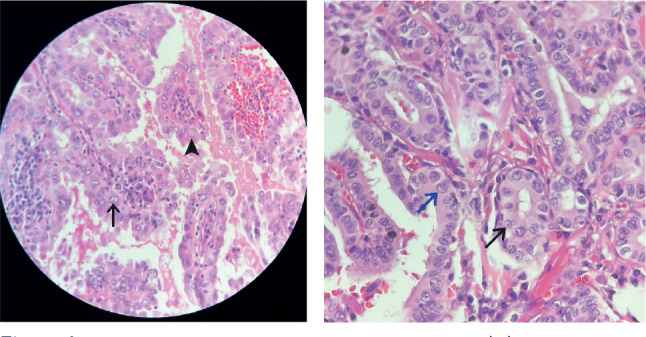

Results: Among the 289 suspicious for malignancy type nodules, 283 were malignant, 5 were benign, and 1 was a noninvasive follicular thyroid neoplasm with papillary-like nuclear features (NIFTP). The most frequently reported cytology features were nuclear grooves and pseudoinclusions; however, they were present in malignant and benign specimens. Statistical analysis revealed that the presence of micronucleoli (p < 0.001) and/or irregular/oval nuclei (p = 0.05) were the characteristics most strongly associated with malignancy. The risk of malignancy was 98% in this study.

Conclusion: The presence of micronucleoli and nuclear irregularity was highly predictive of malignancy according to suspicious for malignancy cytology and were not present in false positive patients. Hence, careful examination of nuclear characteristics can be helpful for identifying true malignancies via suspicious for malignancy cytology. This was significant even when only a qualitative analysis was taken into account.